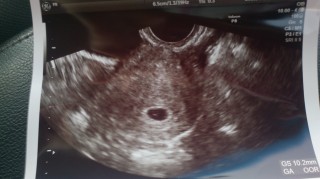

• おなまえまー

• ねんれい29

• 妊娠週5w3d

胎嚢10.2㎜!先週は何も見えなかったのに、モニターを見たら即発見♪先生にも「いいねー!」と嬉しいお言葉頂きました。つわりで吐きまくってるけど頑張るぞー!!